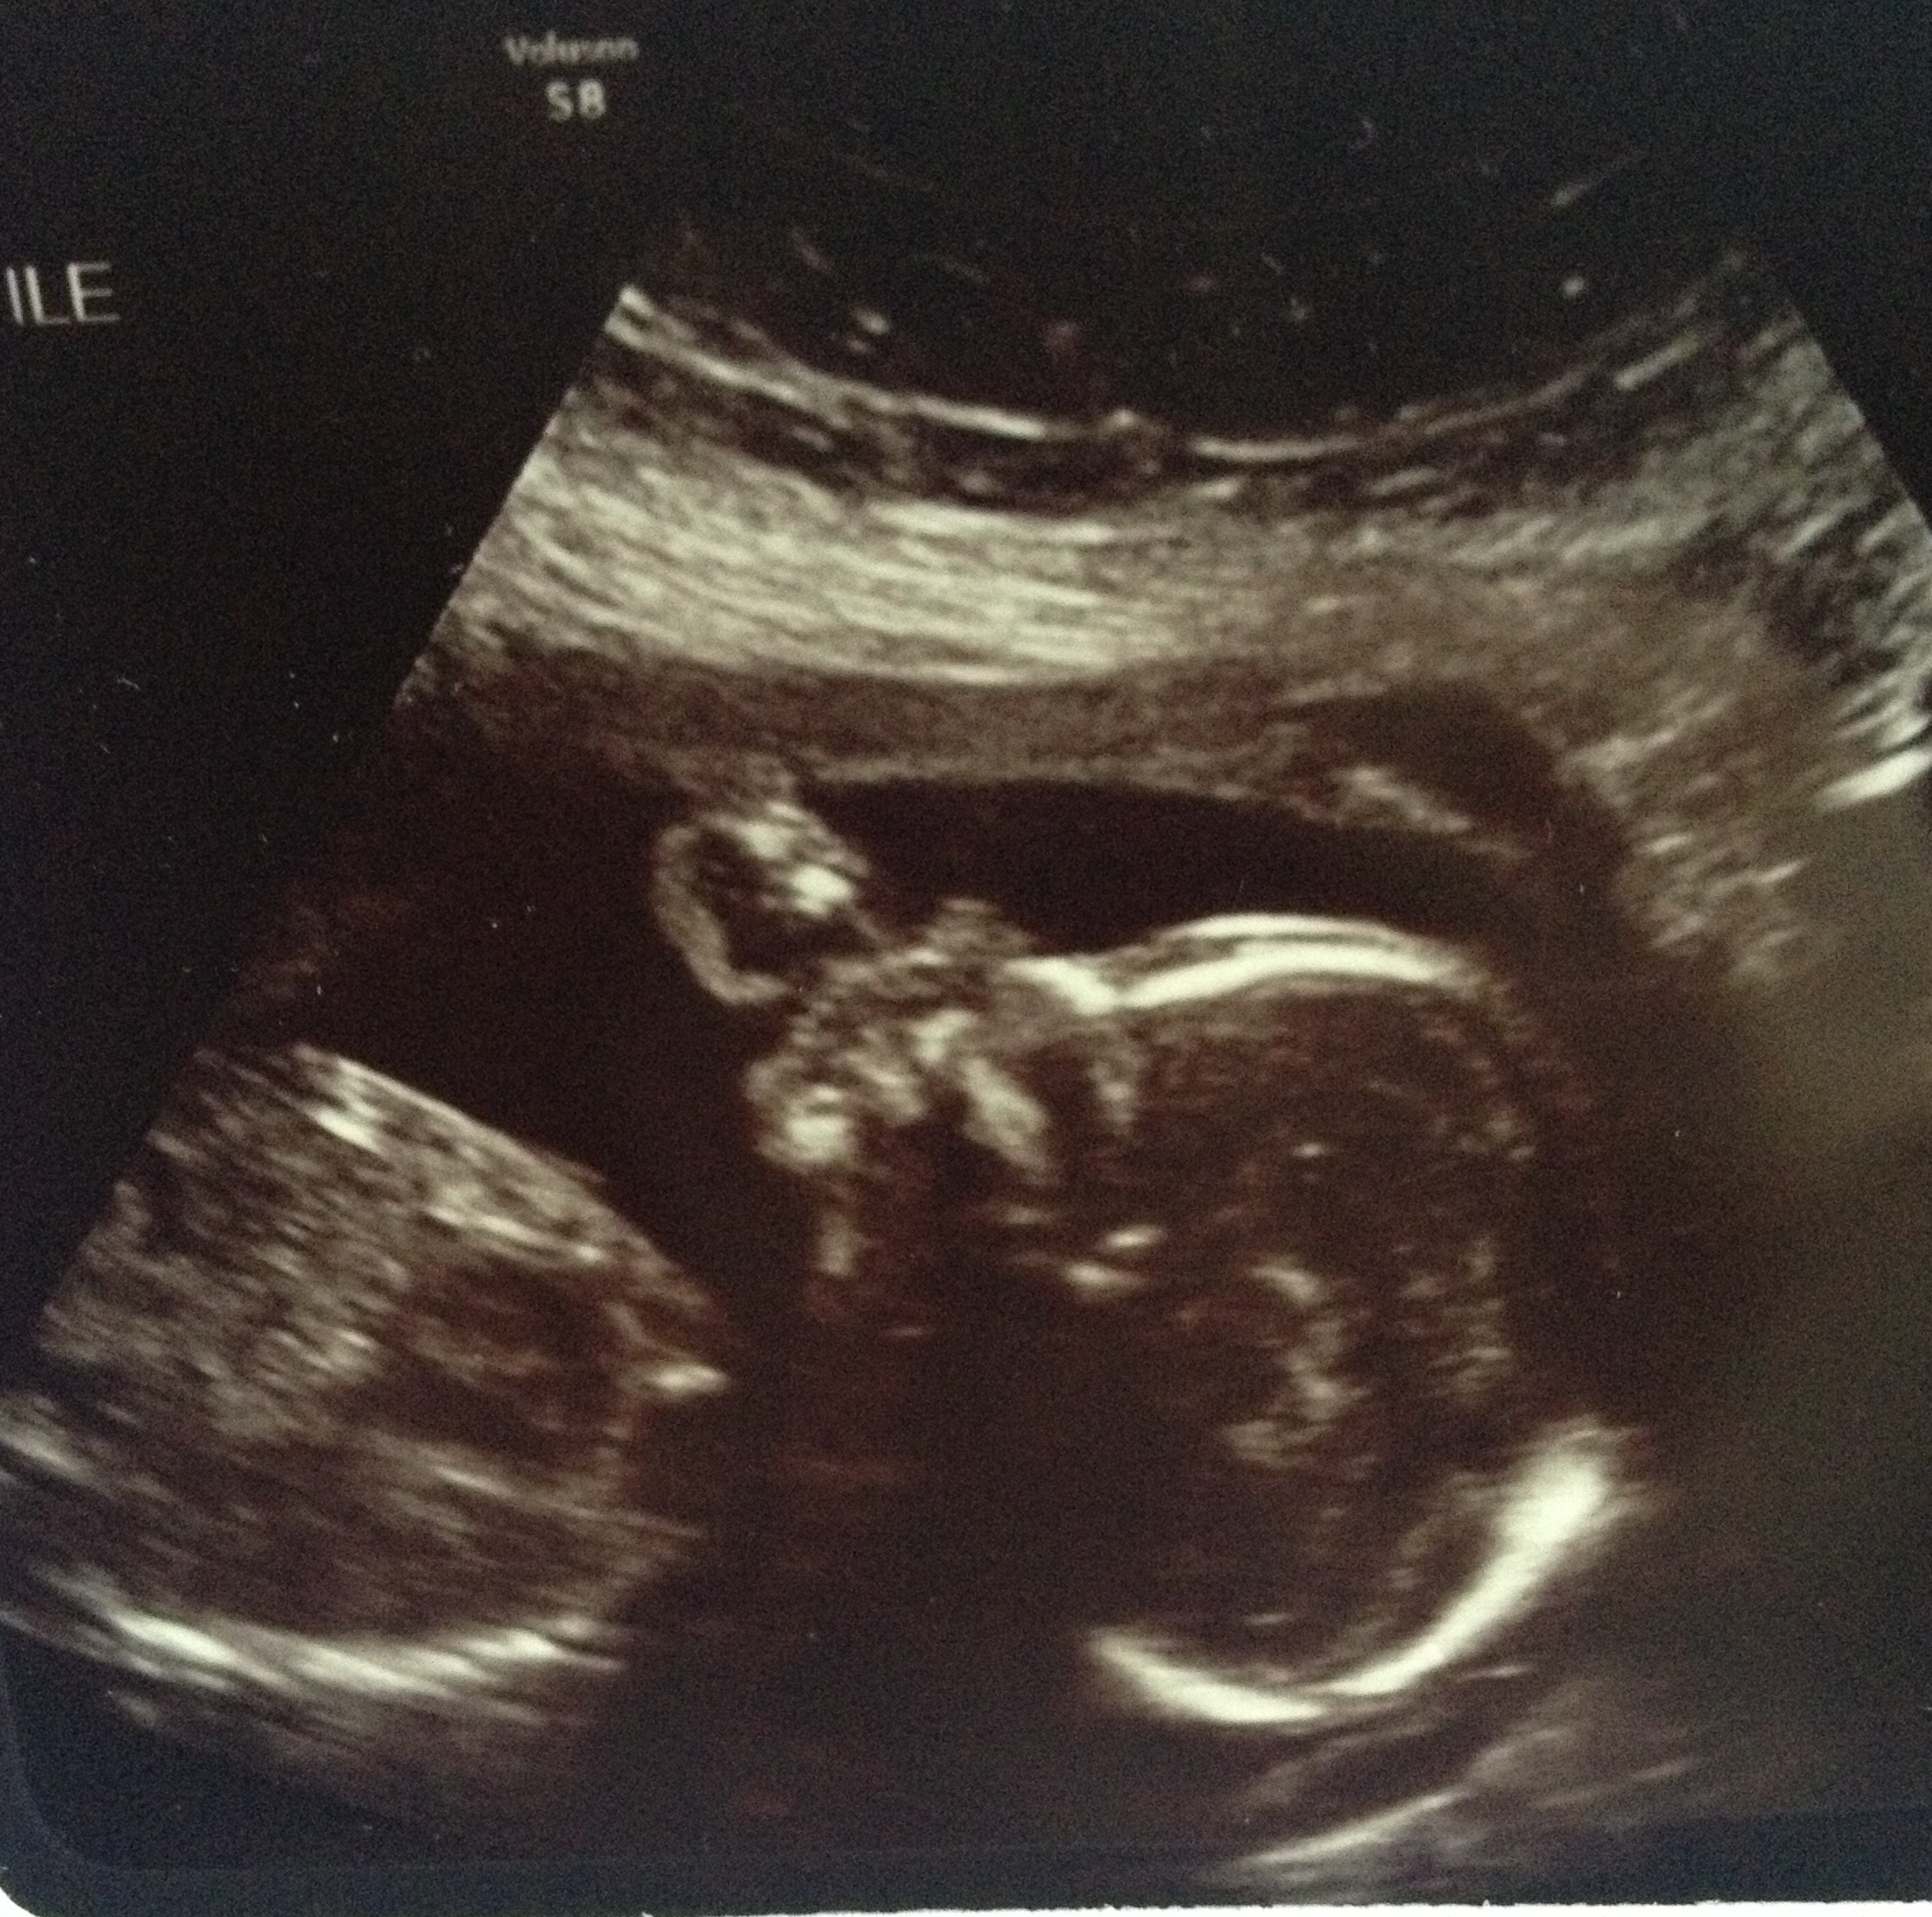

We had ours yesterday! It was so AMAZING to see baby wiggling around in there. Baby was healthy and measuring right on track. We are still team green, guess there is no turning back now! Here's a pic of our cutie pie!